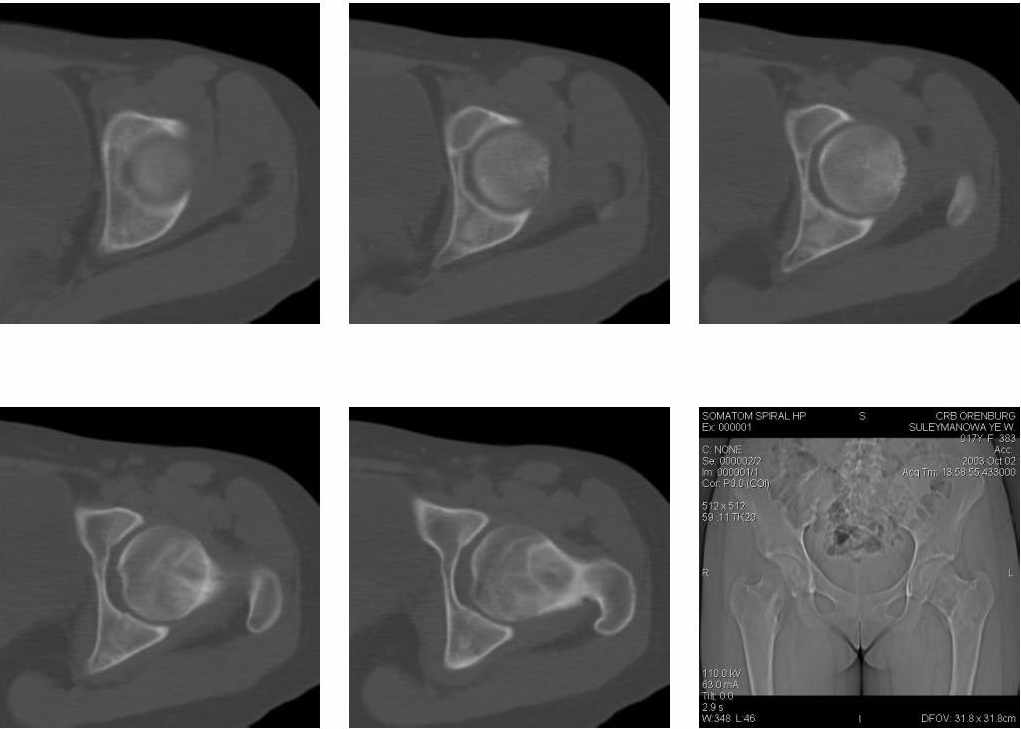

Рентгенограмму приложить не могу, а нас аапараты РУМ-20, а вот увеличенную топограмму пожалуйста.

Кликните для загрузки файла 1.jpg

"У пациентки имеется гигантоклеточная опухоль области шейки и головки левого бедра.

Предпочтительный доступ для биопсии, по нашему мнению, - через большой вертел, не вскрывая суставной сумки.

Оперативное лечение обязательно, т.к. велика вероятность наступления патологического перелома.